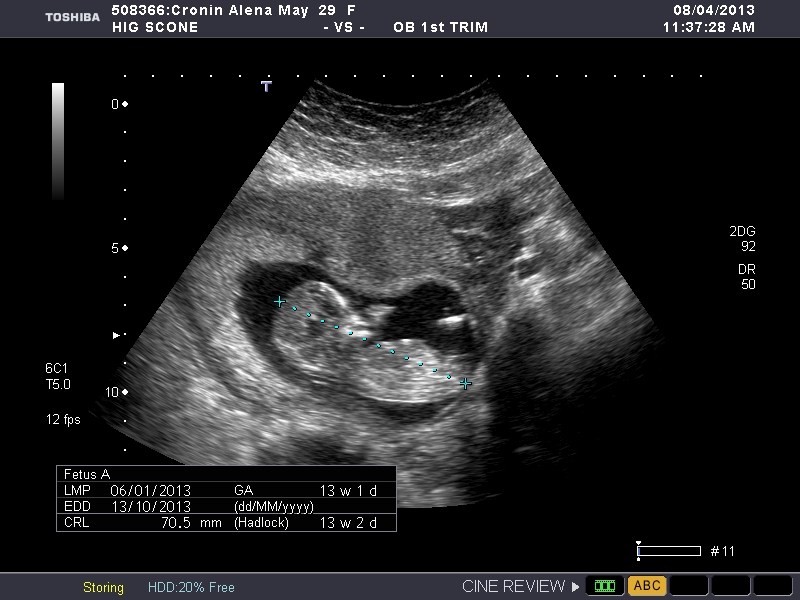

Boy or girl? I am desperate to know. Thanks